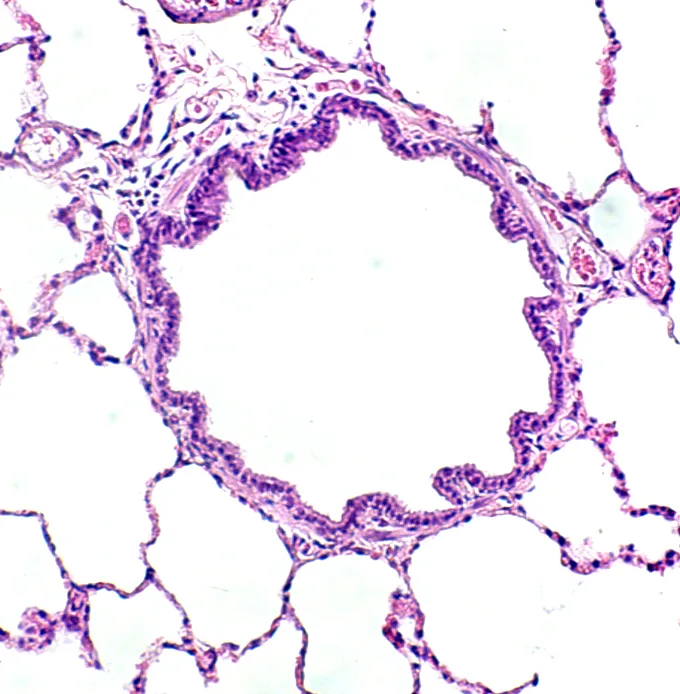

• It is essential to maintain patency of all the ductwork (ie, air passageways from the nares to the smallest bronchiolar ducts) (Figure 2A).

FIGURE 2 A patent airway in a healthy cat (A). An occluded airway from a cat with chronic disease (B). Intraluminal mucus and debris, smooth muscle thickening, numerous inflammatory cells and goblet cells, and subbasement membrane thickening are evident.

• Normal ventilation requires a patent ductwork and functioning air pump. Any clogging, bending, or excessive narrowing of ductwork will substantially reduce airflow into (and out of) the lungs, leading to an obstructive type of breathing pattern.